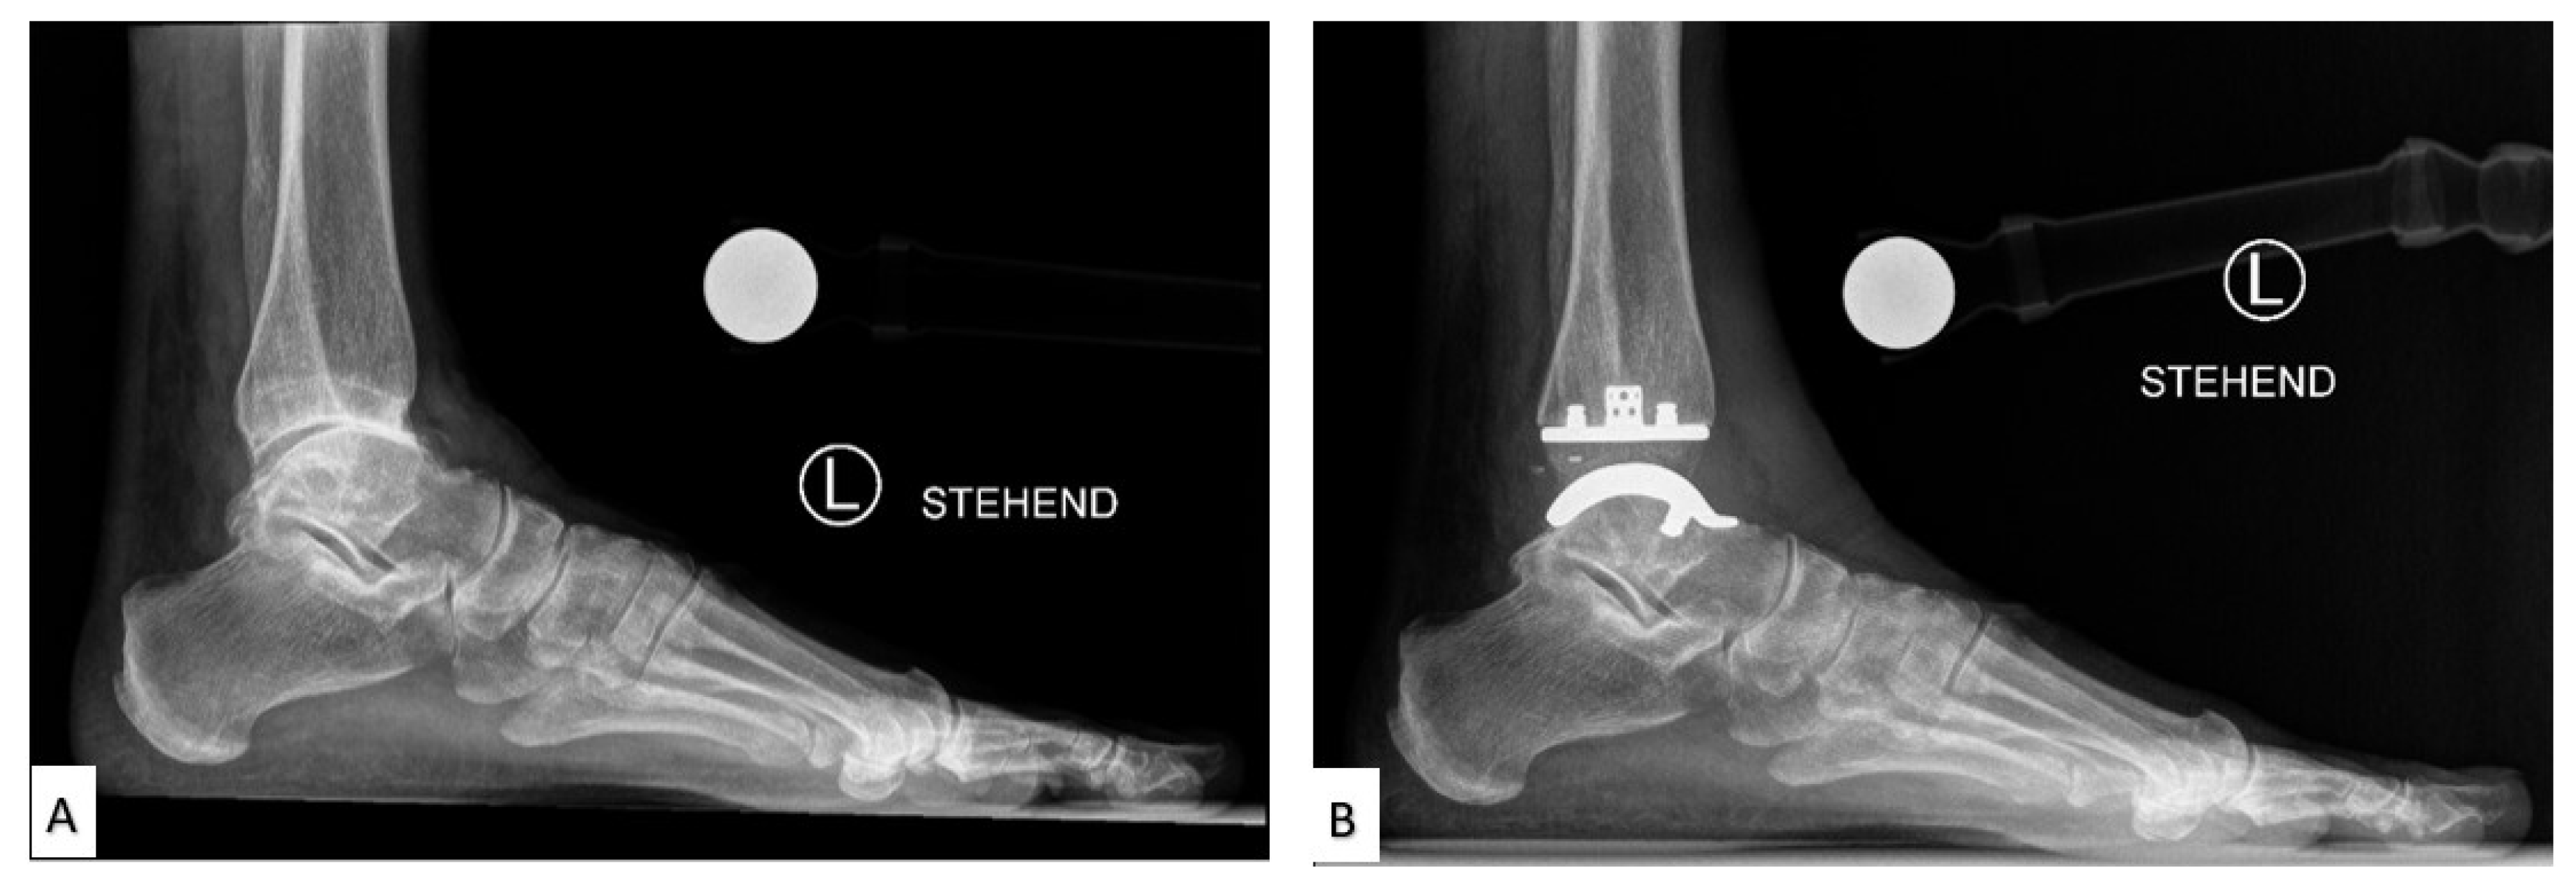

2. Total Ankle Replacement

2.2. Current Total Ankle Arthroplasty Implants